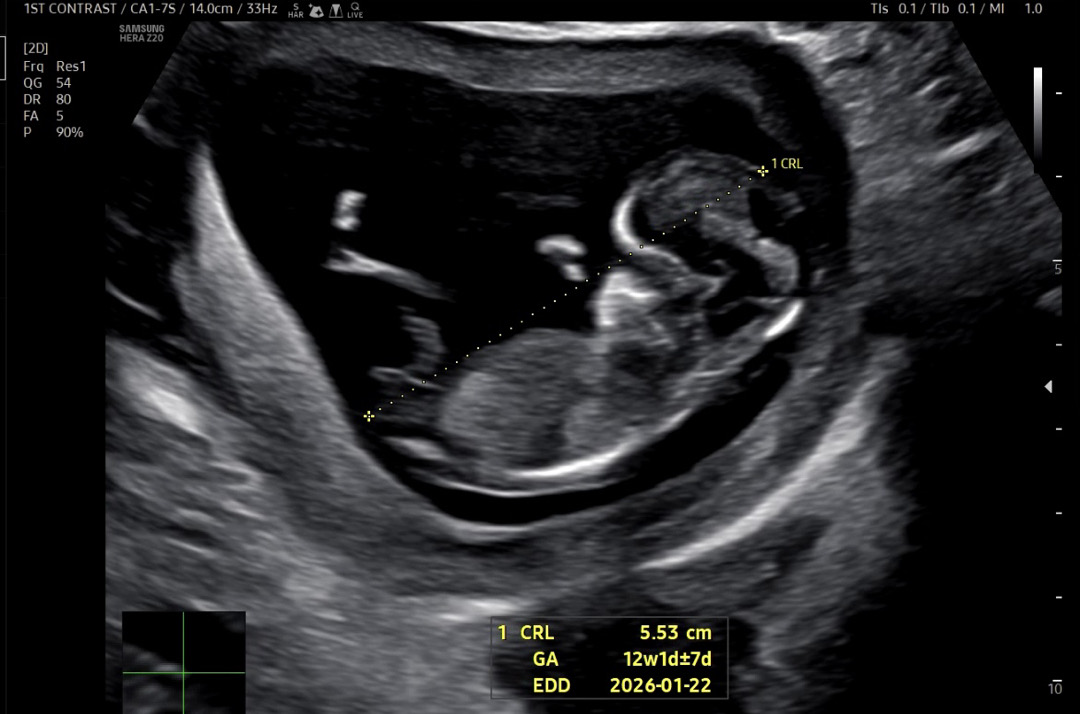

12주 2일 각도법 문의드려요!🩵🫧

ㅠㅠ 성별 너무 궁금해요 한달만 기다리면 되는데 왜이렇게 힘든걸까요.. 각도법 고수분들 의견 한번씩만 부탁드려요🫶🏻

각도로는 아들같아요! 다리사이는 아들도 보였다 안보였다 하더라구요!